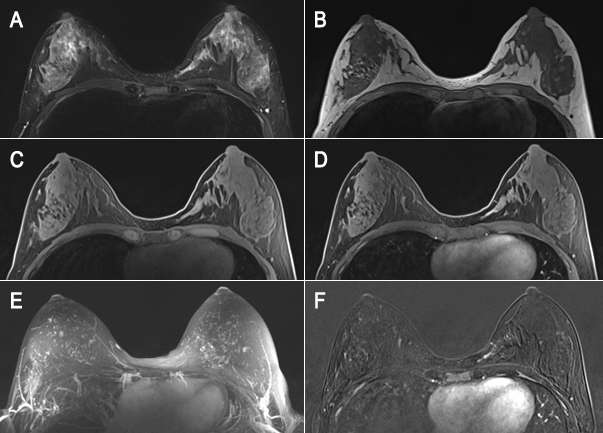

Breast magnetic resonance imaging (MRI) is an invaluable tool for breast imaging practice and interventional procedures when utilized in the appropriate clinical setting. It has the highest sensitivity for breast cancer detection, ranging from 75.2%-100% with a positive predictive value for biopsy comparable to mammography between 11%-40%1. Its high sensitivity is believed to be due to tumor neoangiogenesis, which results in the creation of leaky vessels associated with a breast cancer2. Gadolinium-based contrast agents are able to escape from these leaky vessels and accumulate within a malignancy, allowing for easy visualization on MRI. Thus, unlike mammography, breast MRI is not limited by dense breast tissue. Although benign conditions can also demonstrate enhancement, lesion morphology and enhancement kinetics help distinguish them from cancer.

Breast MRI is indicated for annual breast cancer screening in women with a high risk of developing the disease. High-risk is defined as having a greater than or equal to 20% lifetime risk of breast cancer, which is based on certain criteria that put the patient at risk. Some of the criteria in determining high risk include genetic predisposition, family history and prolonged estrogen exposure. Women without an increased risk for breast cancer benefit less from MRI because the false-positive rate may significantly exceed the cancer detection rate, and further investigation of the findings can lead to additional workups and benign biopsies. However, screening MRI may be appropriate for average-risk women with a history of direct free silicone injections of the breast for augmentation due to the difficulty of mammography in these cases. Other indications in those with genetic predisposition include BRCA mutation carrier (including BRCA1 and 2), an untested patient with a first-degree relative with the BRCA mutation, Li Fraumeni syndrome (p53 mutation) and first-degree relatives, and Cowden and Bannayan-Riley-Ruvalcaba syndromes in first-degree relatives. Lastly, patients who underwent mantle radiation to the chest wall between the age of 10 and 30 years for Hodgkin lymphoma have been shown to benefit from screening MRI due to their increased risk of breast cancer. It is important to note that annual breast MRI screening should be supplemented by mammography and compared to all other available breast imaging modalities because MRI will miss some cancers that mammography can better detect.

There are few circumstances where MRI is used as an adjunct to diagnose equivocal (uncertain) findings on mammography, sonography or physical examination. The first indication is a patient with persistent bloody or cytologically abnormal nipple discharge. MRI may also be useful for a suspicious finding seen only on one mammographic view that is not amenable to conventional biopsy. Breast MRI is also indicated in the evaluation of clinically suspected silicone implant abnormality or rupture. Due to its high spatial resolution and the contrast between implants and soft tissues, it has the highest sensitivity and specificity for implant rupture among imaging modalities and can be used to assess associated complications involving the surrounding breast tissue, chest wall and axilla7. Lastly, it can be used to evaluate patients with unclear but persistent physical examination findings that are mammographically and sonographically occult5.